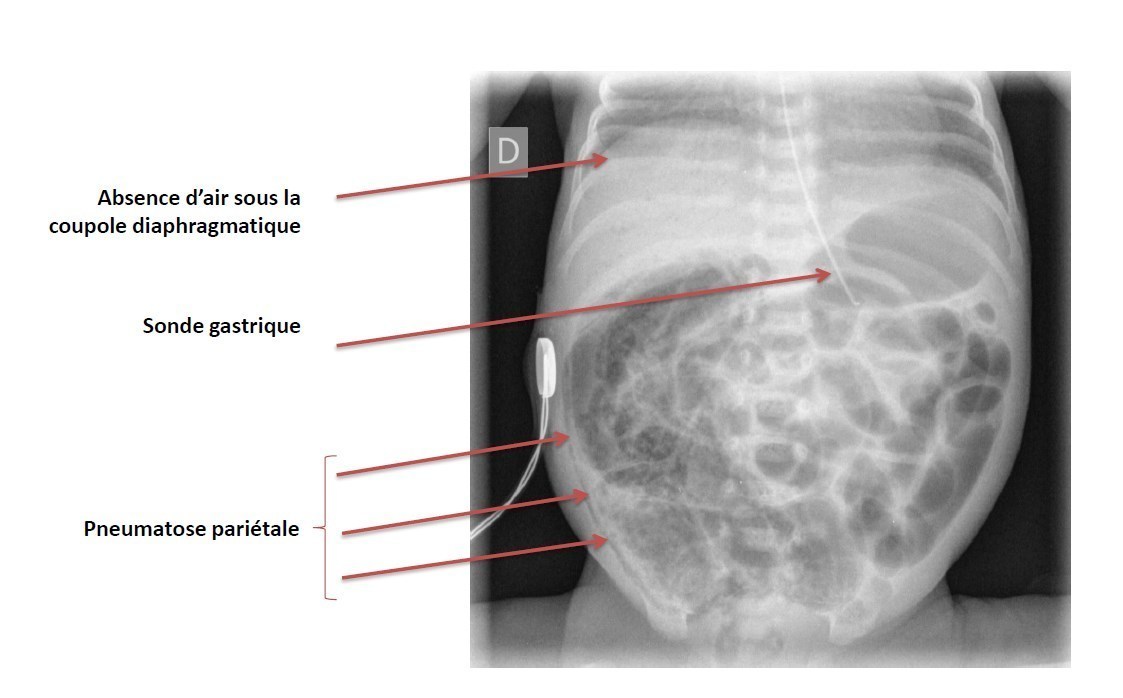

Peut compliquer la ventilation à haute pression nécessaire pour maintenir un volume courant élevé. À éliminer par une radiographie de thorax